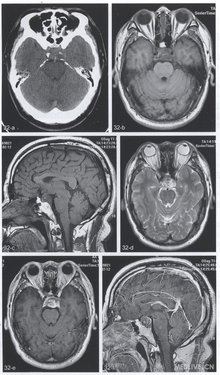

【CT与MRI所见】CT平扫(图32a)显示鞍区偏后、边界欠清的肿块,稍高于脑实质密度,最大径4.0cm,CT值39HU左右,内见斑点状与结节状钙化影,斜坡上端骨质破坏。TiWI(图32b,c)显示肿瘤大部为稍低信号,内见条状及斑点状稍高信号,垂体柄及漏斗受压前缘。双侧颈内动脉轻度包绕。T2WI(图32d)上肿瘤呈不均匀高信号,中央为斑片状稍低信号。增强T1WI(图32e,f)病变不均匀、明显强化,垂体柄及垂体强化正常。

【手术后病理诊断】斜坡脊索瘤。

【影像学特点】影像学特点是斜坡及其邻近的软组织肿块,斜坡或其部分骨质破坏,肿瘤呈膨胀性生长,可见残留骨或钙化。CT表现为斜坡中线区伴膨胀性骨破坏的软组织肿块,边缘清楚,瘤内不规则残留骨或营养不良性钙化。增强扫描轻度到明显强化,不强化区代表黏液样或胶样基质。MRI对肿瘤与邻近结构关系的显示优于CT,但骨质改变及瘤内钙化判断不如CT。由于斜坡骨髓高信号的对照,T1WI可清楚显示肿瘤呈轻度低信号及等信号肿块,瘤内出血或黏液成分表现为高信号,此时行T2*WI或SWI可鉴别两者(出血为低信号)。T2WI上肿瘤为高信号,其病理基础为瘤内含水较多及瘤细胞呈空泡状,肿瘤钙化、出血及黏液样区域为不均匀低信号,有时可见肿瘤内低信号分隔样改变及肿瘤分叶征。增强T1WI显示中度至明显强化,少数轻微强化或无强化,不强化的低信号区使肿瘤呈蜂窝状外观。脂肪抑制技术有利于区别肿瘤强化与斜坡骨髓。软骨样脊索瘤预后较好,其MRI特点为内见短T1、长T2信号成分。脊索瘤对颅内血管如颈内动脉及基底动脉等推移、包绕及狭窄,CTA与MR检查(MRI 与MRA)均可清楚显示。脊索瘤术后易复发,但很少出现颅外转移。